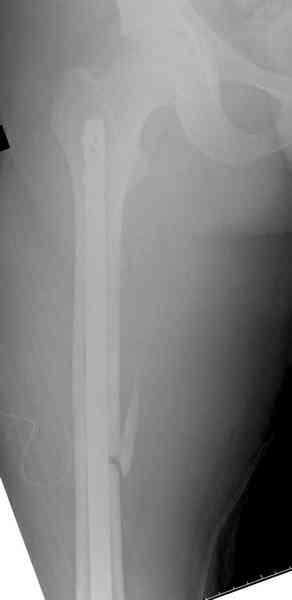

При высокоскоростных переломах редко можно встретить изолированную травму пилона, и в моей практике изолированные травмы большая редкость, поэтому, как дополнение к обсуждаемой теме, решил представить свежий, двухдневной давности случай.

Предыдущей сменой до 4:00 утра по поводу открытого перелома бедра, тибиал плато, пилон и надколенника сделана операция.

Пострадавшему 21 г., травма скоростная, после I&D с расширением раны, на бедре сделана операция ретроградным интрамедуллярным штифтом, остеосинтез с частичной резекцией надколенника и ушивание собственной связки.

На голень наружный фиксатор, рану на бедре ушили (рана была изнутри кнаружи всего 2 см). По протоколу травматических больных, до операции обследован ангиографически, (у больного дистально не смогли определить пульсацию) сосудистый хирург подтвердил проходимость на всем протяжении магистрального сосуда нижней конечности по снимкам ангиограмм.